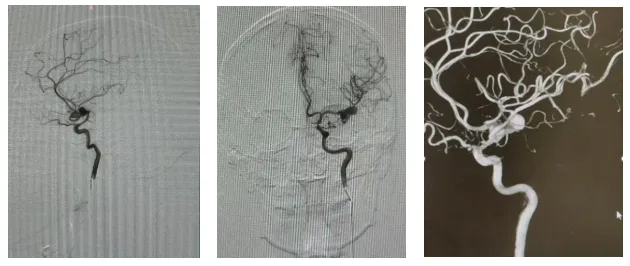

一个瘤颈宽大、形态复杂、累及重要分支血管的大脑动脉瘤,传统的夹闭或介入治疗均无法完成治疗。生死一线间,我院神外五病区吴建梁团队果断抉择,实施了一项犹如“血管移花接木”的血管重建技术:先将远端血管巧妙吻合建立新通路,再彻底切除动脉瘤,最后完成主干血管的高精度吻合。这场集孤立、吻合、重建于一体的复合手术,最终让患者转危为安。术后患者恢复良好,已康复出院。手术的成功标志着我院在复杂脑血管疾病的外科治疗领域达到国内先进水平。

患者为54岁男性,因突发头痛入院。检查发现其左侧大脑中动脉存在一个巨大且形态极其复杂的动脉瘤。该动脉瘤瘤颈宽大,如同树根般包绕着大脑中动脉的两条核心分支,这意味着若直接处理动脉瘤,极易导致分支血管闭塞,引发严重脑梗死,甚至危及生命。

面对挑战,吴建梁教授团队制定了开创性的“血管重建”方案。整台手术犹如在毫米级的血管上进行“移花接木”的显微雕刻,手术全程在先进的血流实时监测系统(FLOW800)护航下进行,确保每一步吻合后血流动力学均保持理想状态。术后影像学显示,患者脑部主要血管血流通畅,动脉瘤完全消失,且未出现任何新发脑缺血损伤。